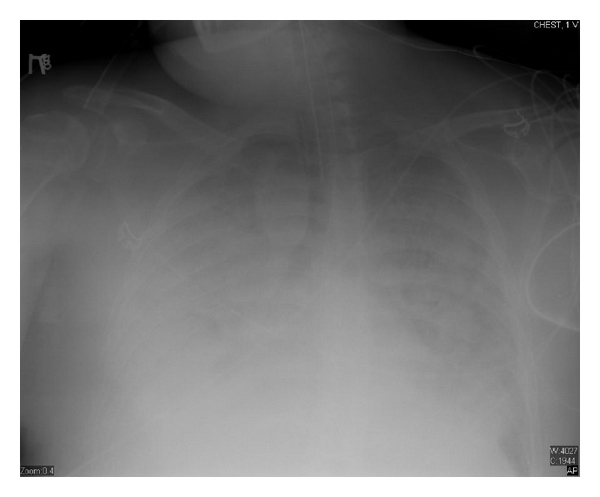

Eighteen days after chemotherapy, the day of recovery of neutropenia, his CXR showed significant worsening with bilateral infiltrates (Figure 2), his fever trended up, and his mechanical ventilation settings (FiO2 and PEEP) increased, he developed acute respiratory distress syndrome (his PaO2/FiO2 was less than 200 with bilateral infiltrates on CXR). Over the following three days, he continued to deteriorate clinically and CXR was getting worse (Figure 3) despite being on appropriate antibiotics and without an evidence of a new infection. Granulocyte colony-stimulating factor (GCSF) was discontinued when the absolute neutrophilic count reached 8000 cell/μL. A transthoracic echocardiogram did not show an evidence of heart failure or valvular vegetation.

Three days after his neutrophil recovery, we concluded that his deterioration must be attributed to the recovering immune system, the diagnosis of paradoxical immune reconstitution syndrome was made, and we started him on methylprednisolone 125 mg IV q 6 hours. Within 48 hours, his fever trended down and we were able to start weaning his oxygen requirements despite no significant change in his CXR (actually CXR did not show a significant change until 10 days later).

After one week, we tapered his steroids down to prednisone 40 mg daily, antibiotics were continued for two weeks, patient was extubated successfully after 18 days of intubation, and CXR day 31 after chemotherapy is shown (Figure 4). He was transferred to the floor, and physical therapy was started. Prednisone was gradually tapered to continue a total period of three weeks of steroids therapy. Patient was discharged to a medical facility to continue occupational and physical therapy.